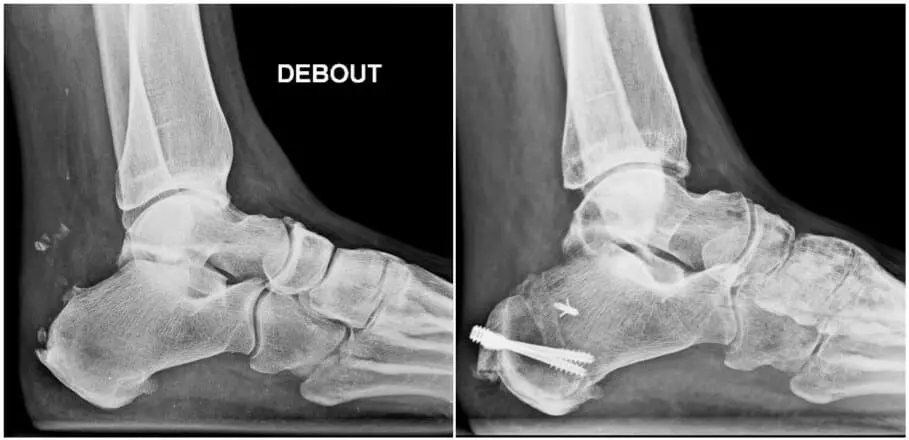

Ce traitement n’est cependant pas toujours suffisant et la chirurgie peut être proposée afin de limiter ce conflit. On peut proposer:

- Une autre technique consiste à supprimer le conflit par une ostéotomie. Cependant, cette procédure entraîne une revalidation de plus longue durée, car on est obligé de fixer les deux fragments osseux à l’aide d’une ou deux vis et la consolidation n’est obtenue qu’après 6 semaines au minimum. La décharge de la cheville durant six semaines est nécessaire et nécessite souvent une immobilisation dans un plâtre.